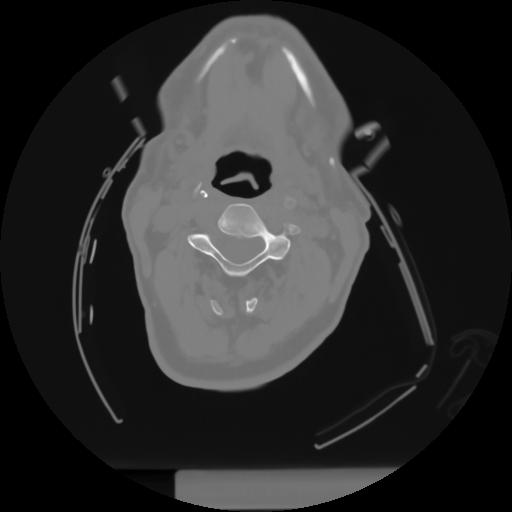

10 P.BLANDAS,,Axial,2.0,P.BLANDAS,,